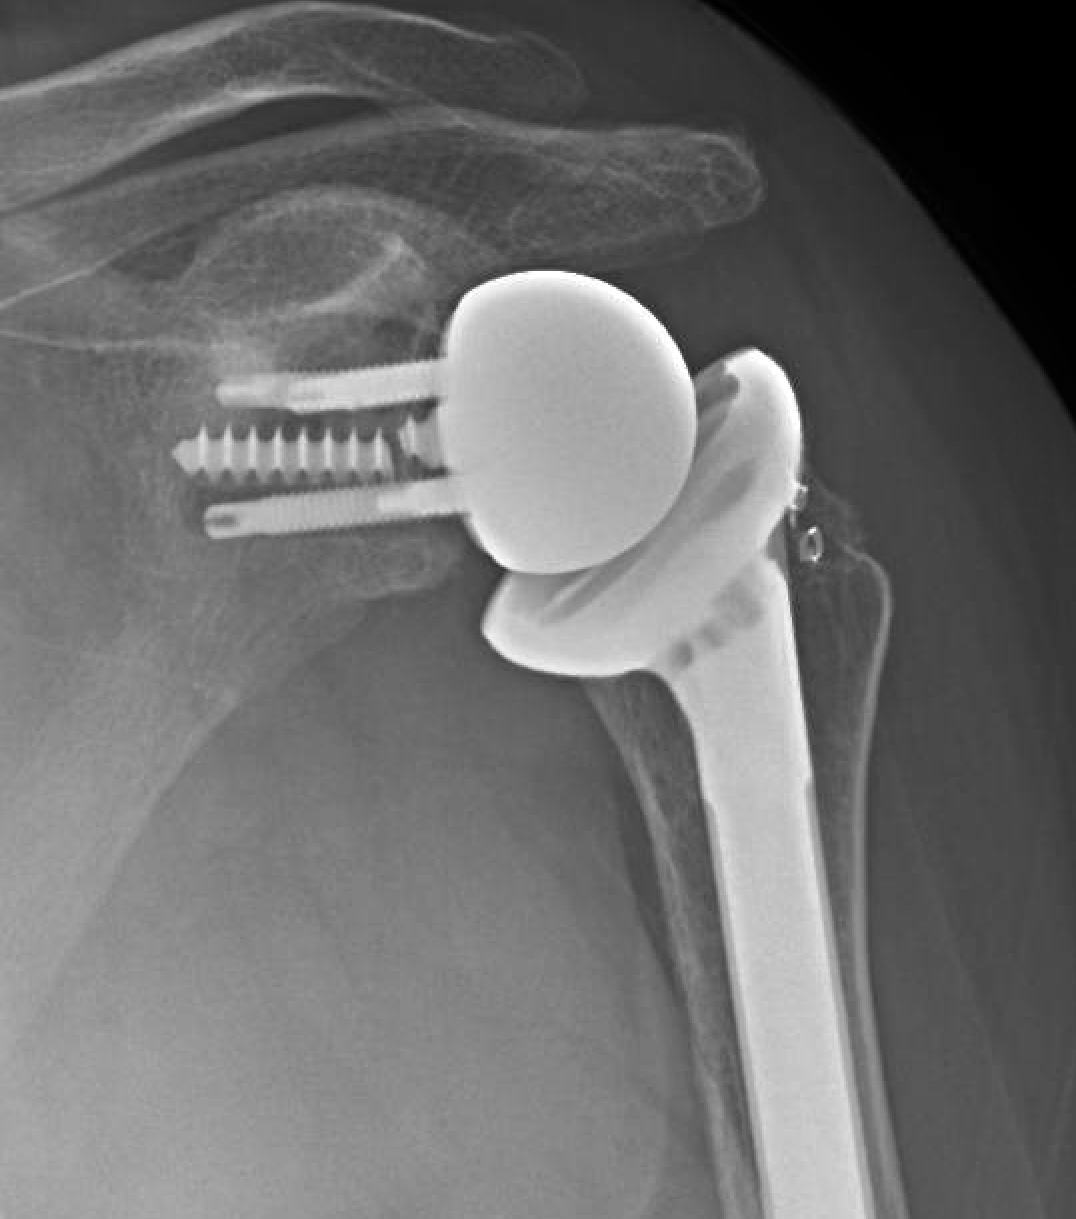

Arthrex FxBridge™ Tuberosity Repair System Reverse Total Shoulder Broken Screw In Shoulder Replacement shoulder fractures most often involve the clavicle (collarbone), proximal humerus (top of the upper arm bone), or the scapula (shoulder blade). a shoulder replacement is a procedure that tries to eliminate the source of pain and dysfunction by replacing damaged parts of the shoulder joint with. with the increasing number of total shoulder replacements, periprosthetic (near the. Broken Screw In Shoulder Replacement.